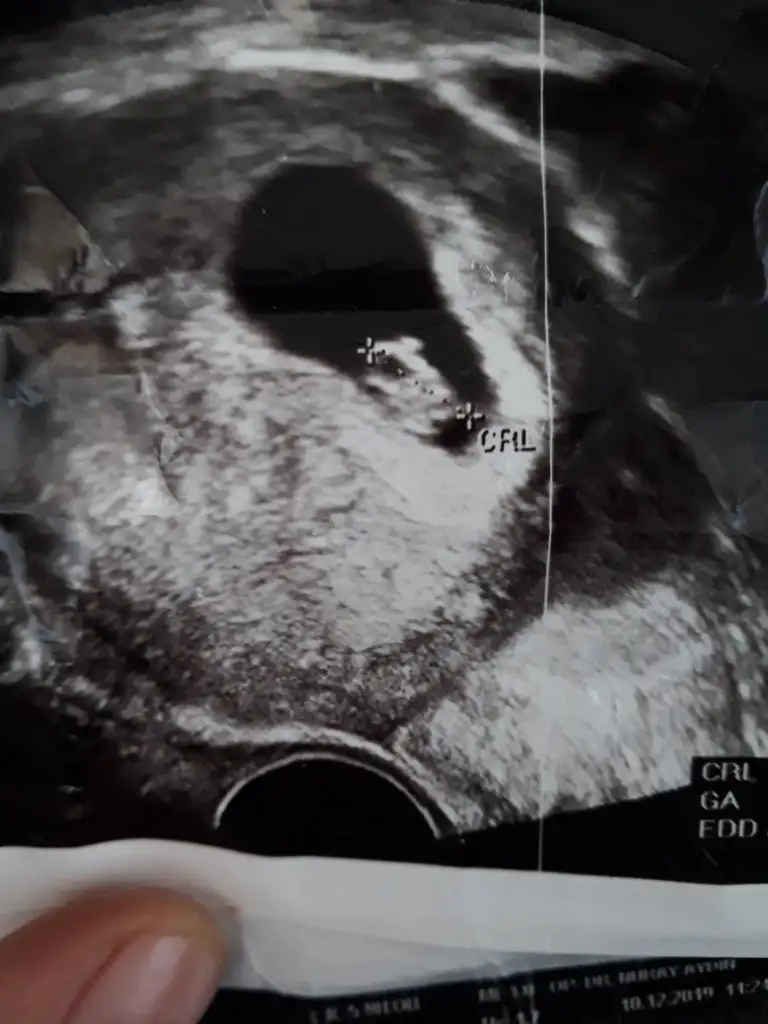

Bu vajinal sagda görünüyor asıl solmuş ve buna göre erkekEki Görüntüle 2574901 bu vajinal bakılan düşük riski olduğu için vajinadan bakıldı

9 haftalık degil ya 5+ yada 6+ olmalı kese içinEki Görüntüle 2574903 bu da karından bakılan 9 haftalık